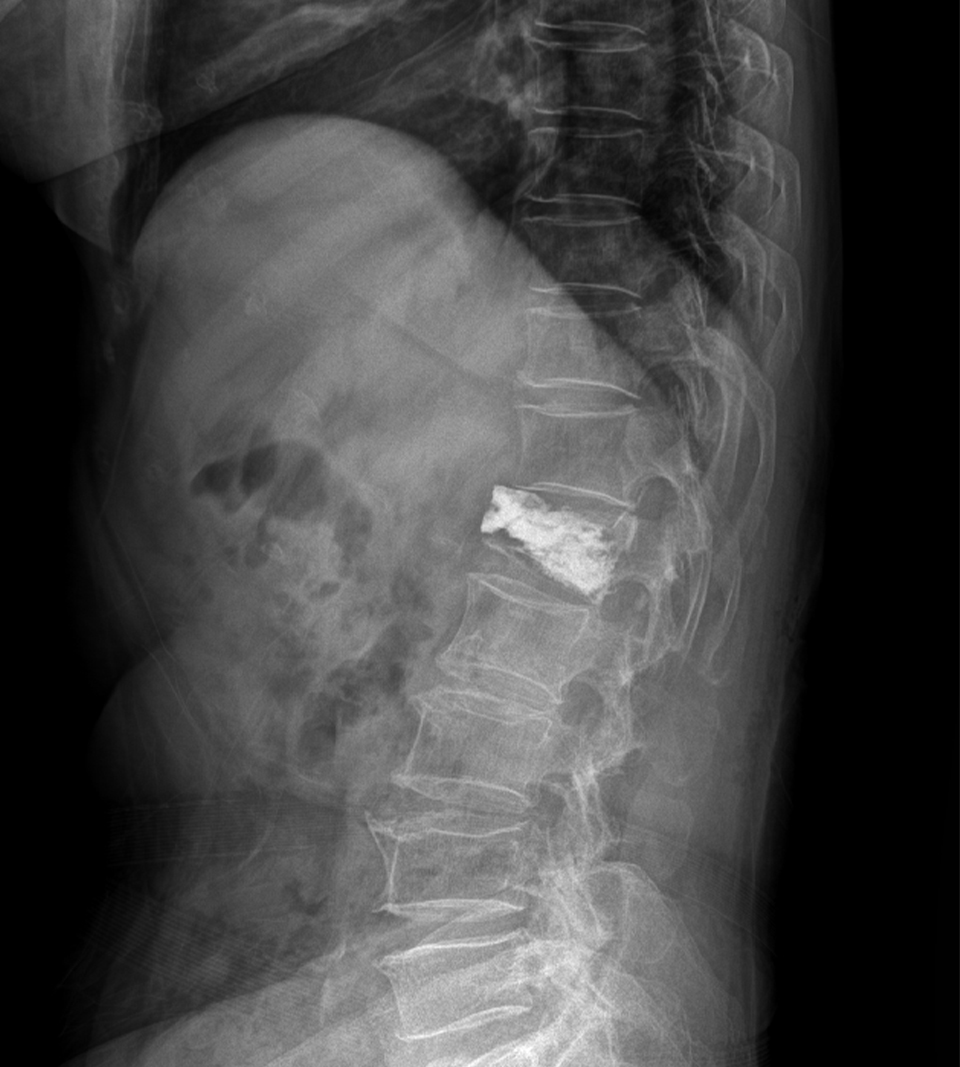

Compression Fracture

<수술전>

- 환자 동의하에 게시된 이미지입니다.